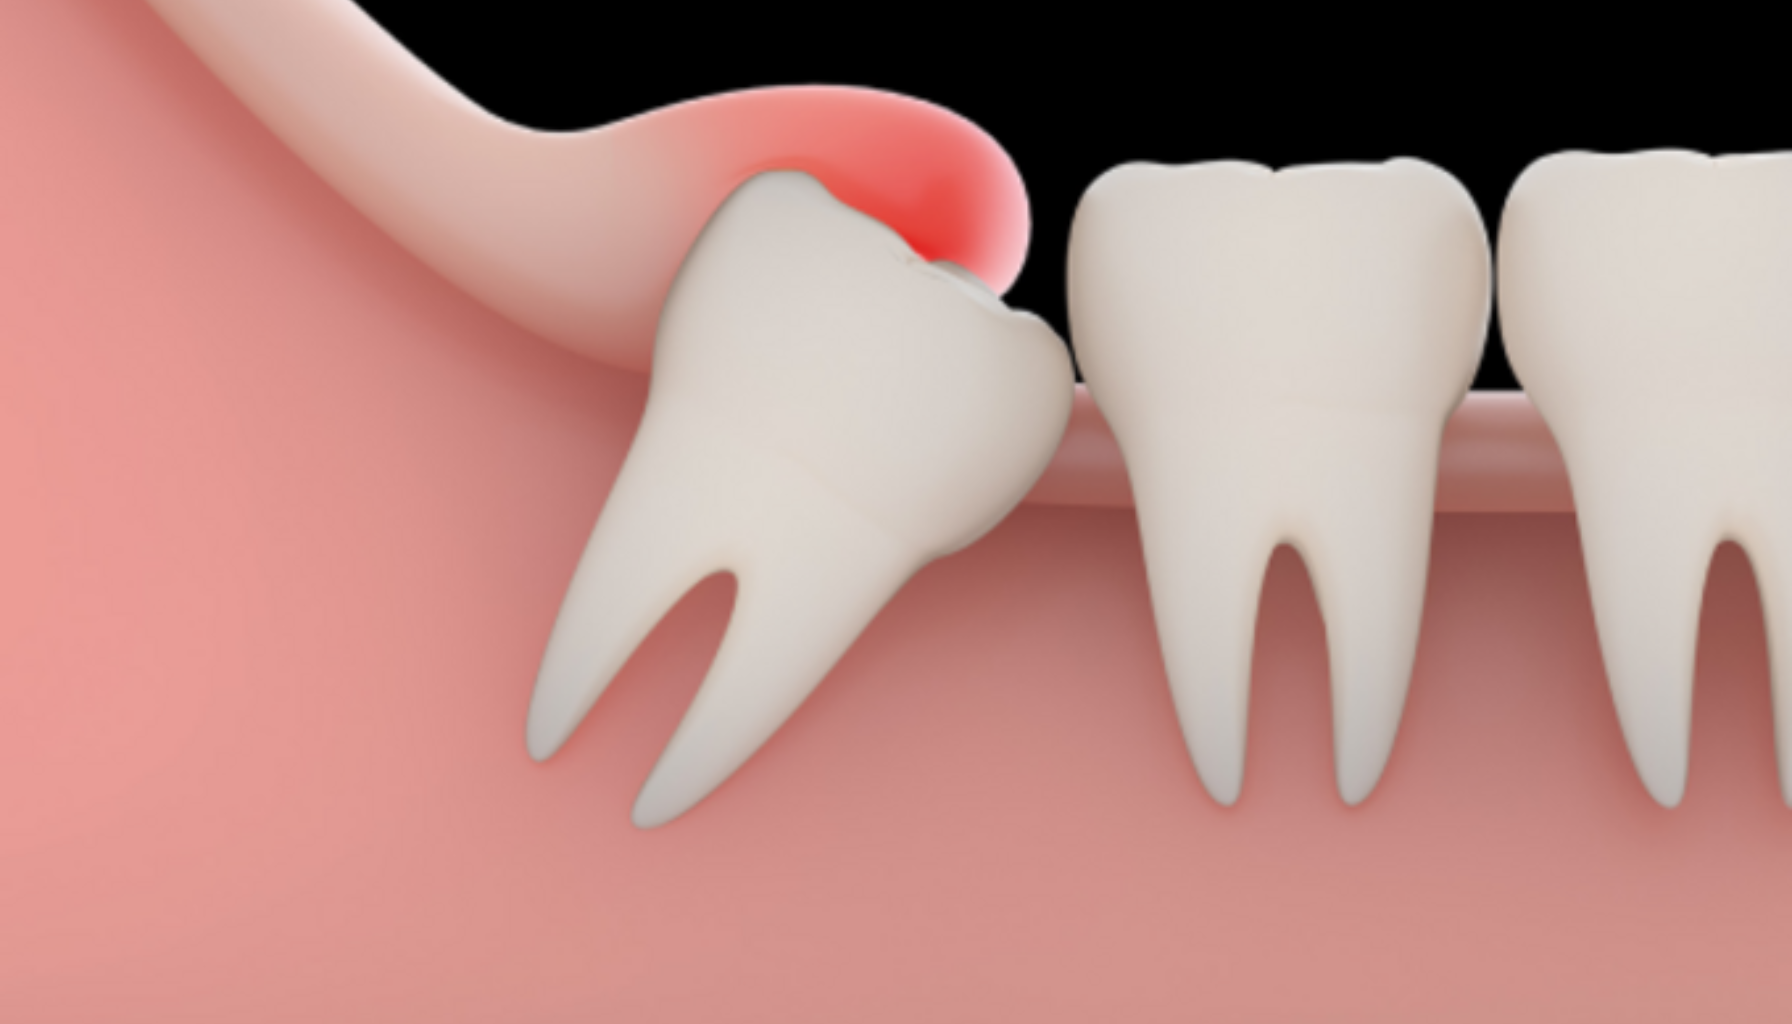

En retinert visdomstann kan i begynnelsen være helt symptomfri, men over tid utvikler mange ubehag. Typiske tegn på problemer inkluderer smerter bak i kjeven, spesielt når du tygger eller åpner munnen. Hevelse og rødhet i tannkjøttet kan tyde på betennelse, og det kan også oppstå en vond smak eller dårlig ånde på grunn av bakterieopphopning. Noen opplever også hodepine eller strålesmerter til øret eller tinningen.

I mer alvorlige tilfeller kan det danne seg en tannkjøttbyll, som gir sterke smerter og feber. Hvis du merker at tannen presser på andre tenner eller forårsaker forskyvning, bør du ta kontakt med tannlege snarest.